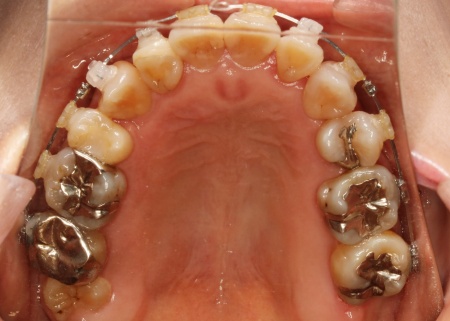

治療後

最後に、歯並びや噛み合わせがしっかりと改善されたことを確認し、治療を終了しました。